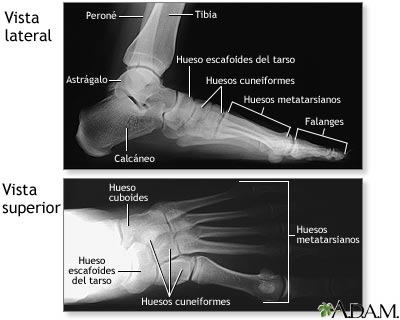

Radiografía del pie normal

Junto con las preguntas de la historia clínica, es posible que el médico necesite tomar radiografías de los pies que ayuden en la elaboración de un diagnóstico con el fin de determinar la causa del dolor de pie. En caso de que el pie esté fracturado, se le colocará un yeso y los dedos fracturados se aseguran con una cinta .